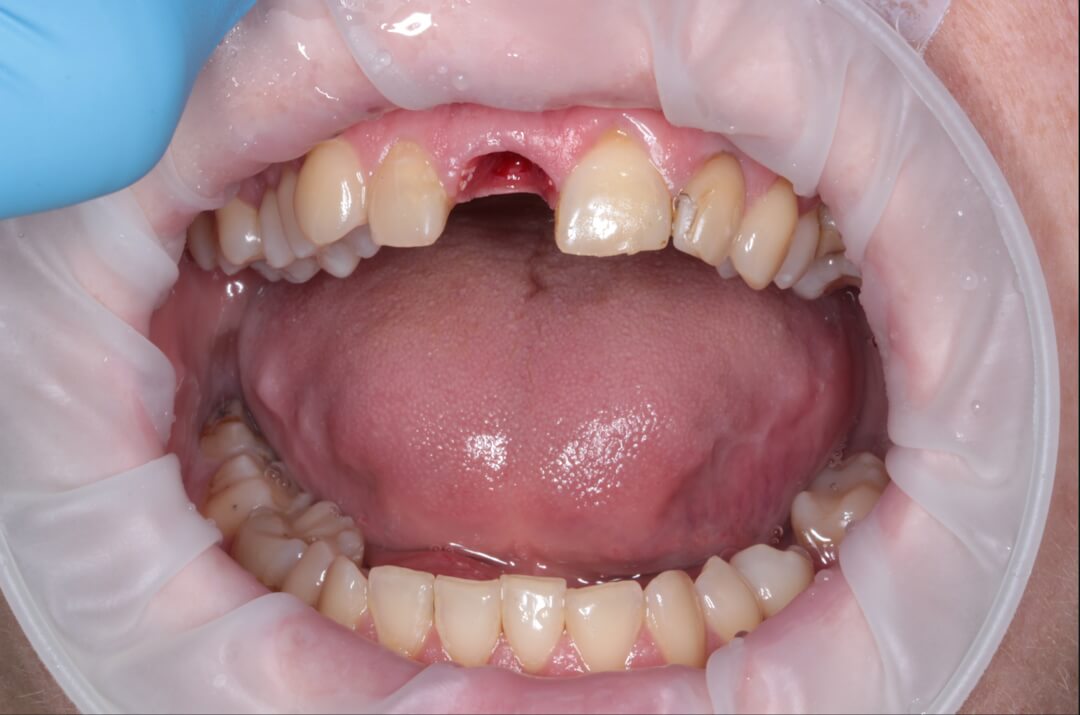

Рис. 4. Вид временной коронки на винтовой фиксации с окклюзионной поверхности. Шахта титанового абатмента закрыта фотополимеризационным материалом.

Зуб был атравматически удален фрагментированием на части с помощью пьезохирургического аппарата и элеватора для максимального сохранения объема костной ткани в месте будущей дентальной имплантации. Во время экстракции врач сохранил целостность вестибулярной стенки альвеолы. Восстановление дефекта мягких тканей в данной области проводилось при помощи туннельной технологии субэпителиальным небным десневым трансплантатом . Устранение дефекта слизистой оболочки и десен способствует стабильному высокоэстетическому результату лечения. После этого хирург осуществляет наращивание костной ткани в вестибулярной области с использованием твердых частиц остеопластического материала. Для предотвращения попадания костного материала на внутреннюю часть имплантата врач устанавливает формирователь десны. Учитывая то, что пациентка по профессии учитель и впереди у нее было много ответственных мероприятий, было принято решение изготовить временную коронку на дентальный имплант непосредственно во время операции, так как все необходимые для этого условия были соблюдены и была такая возможность для этого.